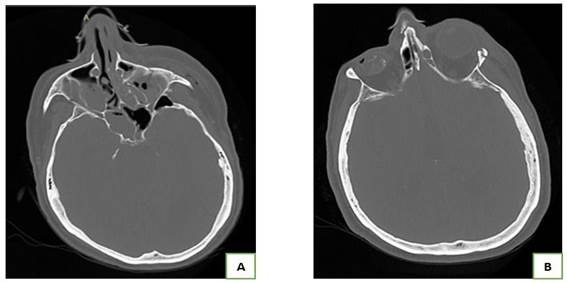

Paciente varón de 73 años, estado basal independiente, con antecedente de hipertensión arterial, 3 días previo a su ingreso, fue evaluado en el servicio de emergencia por presentar caída aparentemente a nivel (no presenciada por los familiares), ocasionándole contusión a nivel frontal, periorbicular izquierdo; dado de alta con medicación sintomática. Ingresó a la unidad de trauma shock por presentar trastorno del nivel conciencia y un episodio de vómito de contenido alimentario. En la evaluación se encuentra al paciente en mal estado general, presión arterial 120/80mmHg, frecuencia cardiaca 109, frecuencia respiratoria 24, saturación de oxígeno 91% con máscara Venturi a FiO2 0.4. Se encontró soporoso, con Escala de Coma de Glasgow (Apertura ocular 1 Respuesta verbal 2 Respuesta motora 5) 8/15, con movilización de las 4 extremidades, se evidenció equimosis periorbicular y edema del párpado izquierdo, herida afrontada con secreción purulenta a nivel de parpado izquierdo, eritema en labio superior; ruidos cardiacos rítmicos de regular intensidad; murmullo vesicular audible en ambos campos pulmonares y roncantes bilaterales. Relleno capilar de aproximadamente 4 segundos, piel marmórea predominante en extremidades inferiores. La gasometría arterial mostró acidemia leve por acidosis respiratoria e hipoxemia parcialmente corregida y lactato elevado, se enviaron muestras a laboratorio para exámenes séricos (Tabla N°1). Se planteó los diagnósticos de insuficiencia respiratoria hipoxémica - hipercapnica probablemente atribuido a proceso neumónico, trastorno del sensorio a descartar hemorragia intracerebral por traumatismo encefalocraneano. Se colocó vía periférica e infusión de solución salina a goteo y se procedió a intubación utilizando fentanilo, midazolam y se conectó a ventilación mecánica con parámetros protectivos. Se trasladó a sala de imágenes, se realizó tomografía cerebral y torácica sin contraste, la cual no mostró lesión isquémica ni hemorrágica cerebral aguda, el parénquima pulmonar sin infiltrados ni efusión pleural (Figura N°1).

Figura 1: A. Tomografía de tórax sin contraste que no muestra lesiones focales significativas del parénquima pulmonar, ni efusión pleural ni pericardio. B. Tomografía de cerebro sin contraste, no se evidencia signos de isquemia ni hemorragia. aguda.